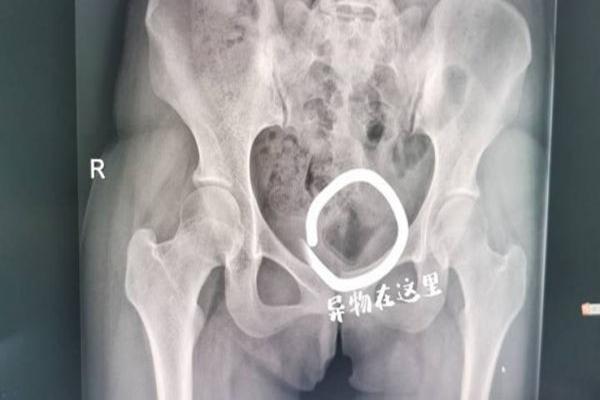

Bác sĩ kiểm tra và phát hiện có dị vật nằm sâu trong âm đạo của Tiểu Dương, vật thể nhẵn và không thể lấy ra bằng các dụng cụ y tế thông thường. Bác sĩ Cao Kiến Tùng cho biết, dị vật lưu lại trong cơ thể bệnh nhân khá lâu nhưng rất may vị trí không sâu.

Nhờ công nghệ sóng siêu âm hỗ trợ, sau nhiều lần thăm dò, cuối cùng dị vật trong cơ thể Tiểu Dương được đưa ra ngoài bằng kẹp phẫu thuật. Hóa ra, dị vật cặp đôi nhét vào vùng kín trong lúc ân ái là nắp đậy mỹ phẩm có chiều dài 5cm và chiều rộng 3cm.